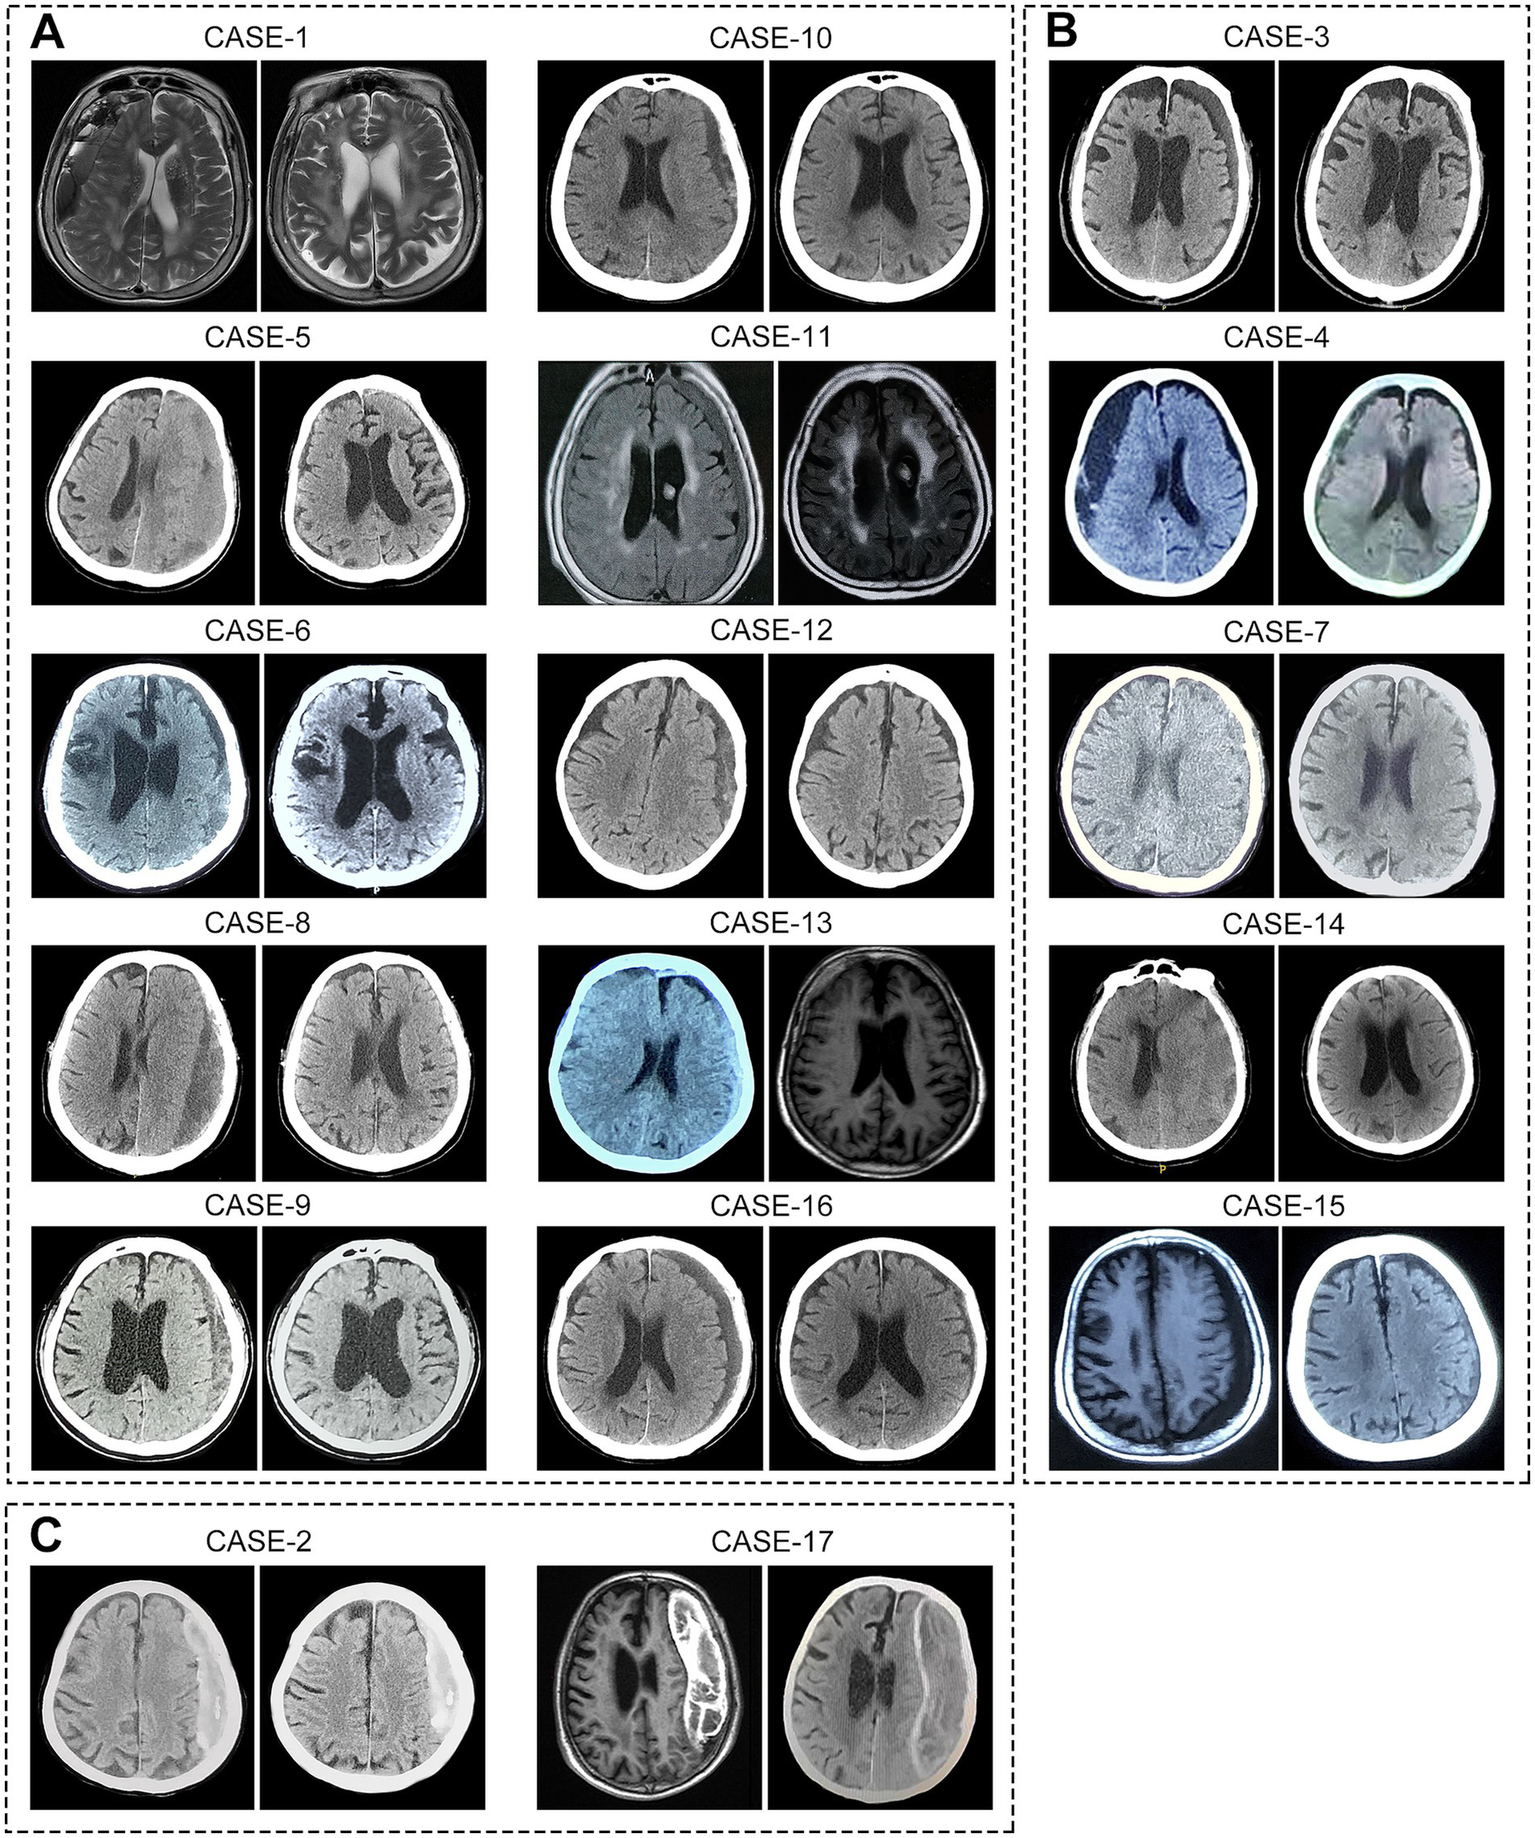

Following atorvastatin-based conservative treatment, CT/MRI imaging revealed complete hematoma absorption in 10 patients and a significant reduction in five (Figure 2). However, two patients with calcified hematomas showed no evidence of CSDH absorption; despite this, their neurological symptoms fully resolved, and atorvastatin was discontinued at the six-month follow-up. Additionally, compared to initial neurological assessments at the time of CSDH diagnosis, both mRS and MGS-GCS scores showed significant improvement following treatment (Table 2). Upon admission, nine patients (53%) presented with severe disability (mRS score 4–5), all of whom exhibited progressive improvement, with mRS scores reducing to 1–3 after treatment. Likewise, MGS-GCS grades decreased in all 17 patients, with a significant relief of neurological symptoms at the six-month follow-up.

Figure 2

Imaging of hematomas before and after treatment in 17 super-aged CSDH patients. After receiving atorvastatin-based conservative treatment, (A) 10 patients showed complete hematoma absorption, (B) 5 patients exhibited significant reduction in hematoma size, and (C) 2 patients with calcified hematomas showed no apparent absorption.